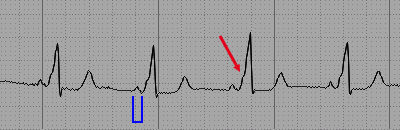

Introduce tu texto aquí... SCASEST